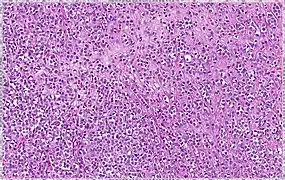

Histopathology of invasive lobular carcinoma (ILC), next to lobular carcinoma in situ (LCIS)

Histopathology of invasive lobular carcinoma (ILC), next to lobular carcinoma in situ (LCIS).jpg.webp) Invasive lobular carcinoma demonstrating a predominantly lobular growth pattern

Invasive lobular carcinoma demonstrating a predominantly lobular growth pattern Lobular breast cancer. Single file cells and cell nests.

Lobular breast cancer. Single file cells and cell nests.